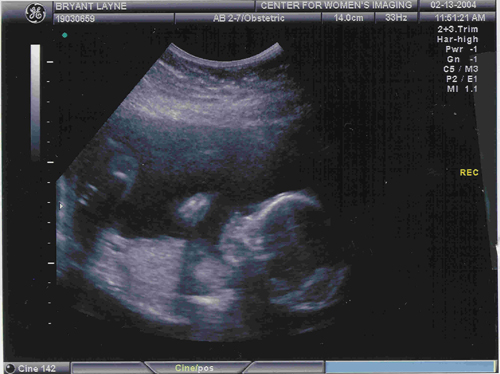

Eleanor's Second Ultrasound

This picture was taken in February, 2004, about eleven weeks after her first.